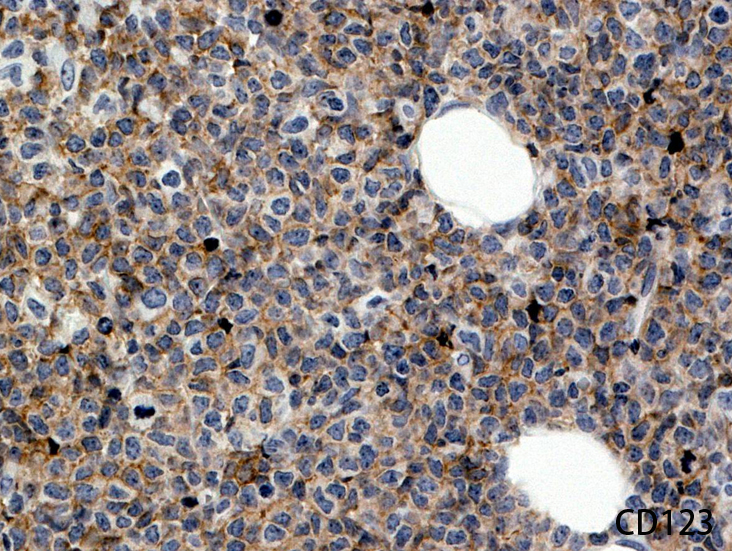

Fig04, Fig05は腫瘍細胞の拡大像。大型異型細胞の出現が認められる。腫瘍細胞はCD4+, CD56+, CD123+(Fig.06)

CD123a.jpg

Fig.04Fig.05Fig.06 CD123